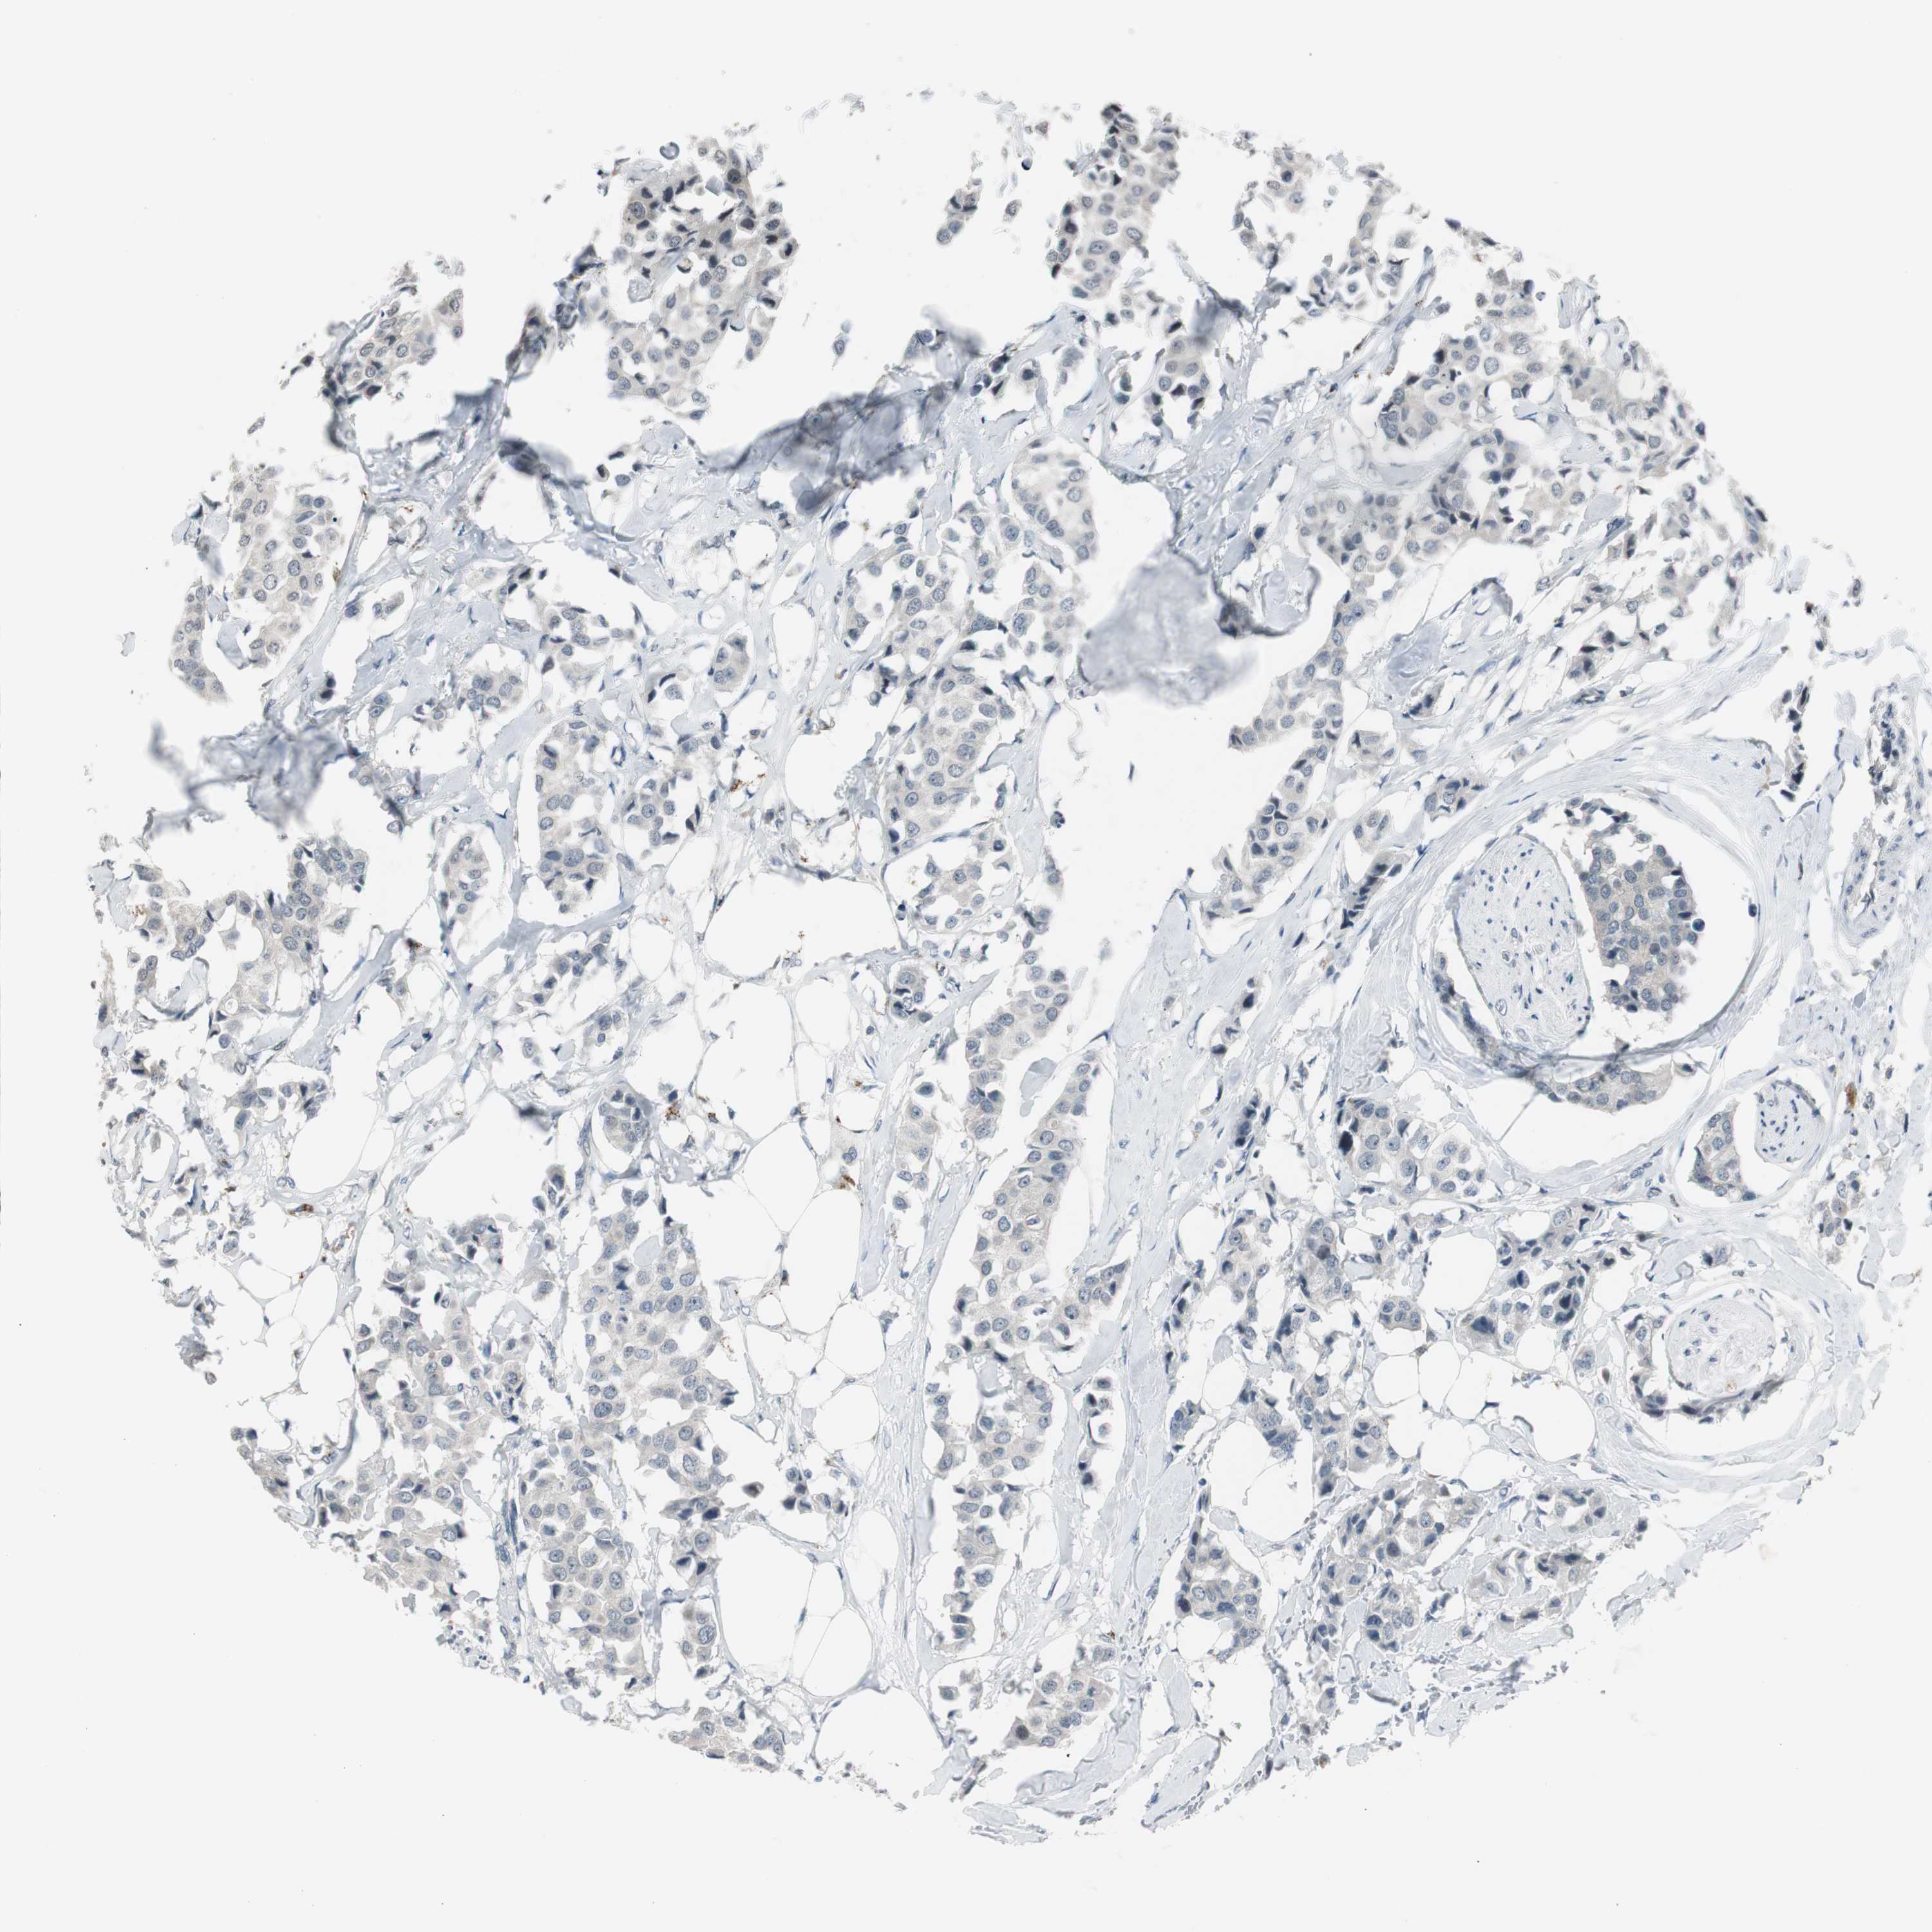

BRCA TCGA BRCA VALIDATION PROTEIN EXPRESSION

ANTIBODIES

AND

VALIDATION